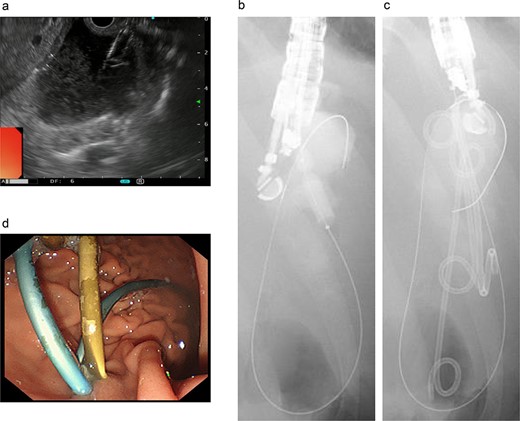

Endoscopic retrograde pancreatography (ERP) was performed, and contrast leakage was observed in the pancreatic body, leading to the diagnosis of grade III pancreatic injury (Fig. 3a). Although the guidewire was successfully passed beyond the injury site to the caudal pancreatic duct, cannula passage proved challenging (Fig. 3b). Consequently, a 5 Fr EPS was placed in the region of the pancreatic head (Fig. 3c).

ERP and EPS on the fourth day. (a) Leakage of the contrast medium was observed in the pancreatic body, leading to the diagnosis of grade III pancreatic injury. (b) The cannula had difficulty passing through the injury site; however, the guidewire was observed to have passed beyond the pancreatic duct injury site at the pancreatic tail. (c) A 5 Fr-5 cm EPS was placed in the region of the pancreatic head.